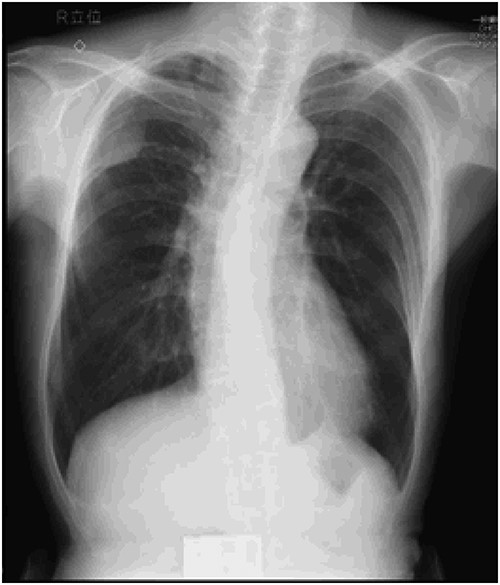

An asymptomatic 79-year-old male who was diagnosed with a chest wall tumor, which had been detected by an X-ray of a health examination, presented to our hospital for surgical intervention. He had no relevant past medical history, including malignant neoplasm or radiation therapy. No mass was palpable. The chest X-ray revealed a tumor shadow of 3 cm in diameter in the right upper lung field (Fig. 1). Chest contrast computed tomography (CT) revealed a well-circumscribed tumor shadow measuring 37 × 27 mm in the posterolateral region of the right sixth intercostal space, the size of which had increased 1.5 times in the previous 3 months (Fig. 2). Thoracic magnetic resonance imaging (MRI) revealed a solid tumor that was enhanced by gadolinium on T1-weighted imaging (T1WI). T2-weighted imaging (T2WI) showed a homogeneous mass with iso-intensity. The tumor was inhomogeneous while demonstrating a maximum standardized uptake value (SUV) of the [18F]-2-deoxy-D-glucose (FDG) uptake under positron emission tomography (PET), with a range of 3.4–4.1 (Fig. 3). There was no significant uptake at other sites, including the mediastinal lymph nodes. No tumor-markers (CEA, proGRP and CYFRA) were detected in a laboratory analysis. Based on these examinations, we suspected a neurogenic tumor, especially schwannoma, and we opted for surgical resection. Considering the fact that ~10% of neurogenic tumors are malignant and the FDG uptake was heterogeneous, we planned to perform an intraoperative frozen section examination. We first performed tumor resection. The operation was performed in the left lateral position under general anesthesia. A 30° viewing angle thoracoscope was set at the middle axillary line of the seventh intercostal space. The tumor was smooth, slightly solid and covered with pleura (Fig. 4). We added a 4-cm incision just above the tumor, while verifying its location through the thoracoscope, and easily removed it from the chest wall. The tumor was diagnosed as sarcoma based on the frozen section examination. Therefore, we added removal of a portion of the sixth and seventh right rib. We excised the chest wall with a 2-cm margin from the lesion, confirming an adequate length through the thoracoscope. Chest wall reconstruction was performed with DUALMESH® (Gore, Flagstaff, AZ). On the cut section, the tumor appeared as solid, smooth-surfaced and encapsulated whitish mass of 3.7 × 2.7 cm in size. Upon microscopic examination, the tumor was composed of fascicles of highly atypical spindle cells mitotic figures exceeding 15 per 10 high-power fields. Immunohistochemistry was positive for αSMA (Fig. 5), desmin and caldesmon and was negative for S-100 protein (data not shown). All margins were negative, and no invasion to the peripheral organs was seen. We concluded that the tumor was leiomyosarcoma of the chest wall. He was discharged on post-operative day 10 without any complications. Since we considered that curative resection had been achieved, no adjuvant therapy was performed. He is still being followed up; however, liver and multiple lung metastases were detected at 5 years after surgery.

Preoperative chest X-ray: tumor shadow in the right upper lung field.